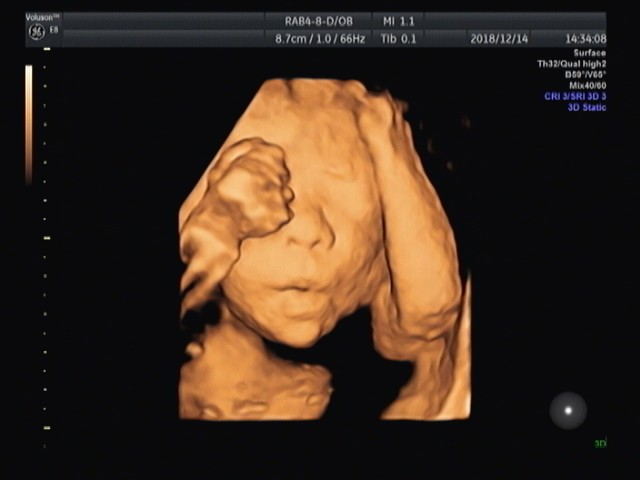

胎兒四維超聲檢查